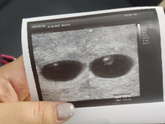

Сейчас была на УЗИ просто убедится что беременность не внематочная. Эмбриончика не видно ещё , ПЯ 9.7мм сказала 4 недели срок, по месячным у меня 5.3 . Через 10 дней прийти снова сказали должен быть эмбриончика и возможно сердечко ❤